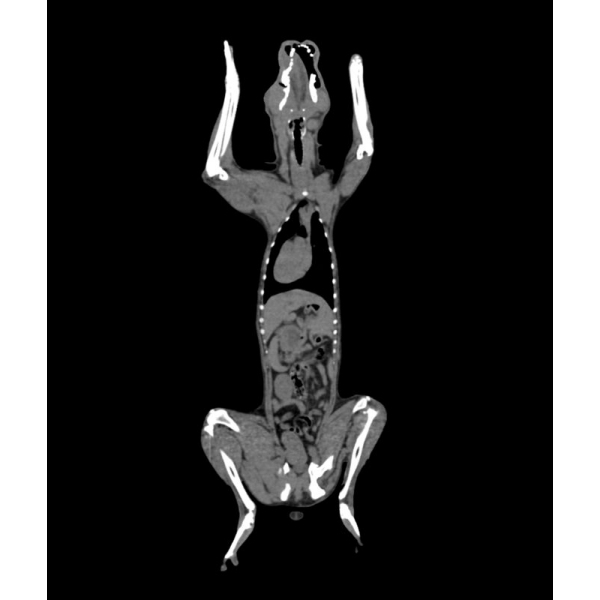

Fantom zagotavlja realistično simulacijo psa brez kontrastnega sredstva. Kosti in mehka tkiva so prikazana verodostojno z realističnimi vrednostmi CT za vsa tkiva pri 120 kVp napetosti cevi v CT. Zračni prostori so zapolnjeni s celuloznim polimernim kompozitom s približno -80 Hounsfieldovimi enotami.

Če se bo fantom uporabljal predvsem pri drugih napetostih cevi (npr. 100 kVp), se lahko po potrebi ustrezno prilagodi kalibracija vrednosti CT ? Fantom zagotavlja tudi realistične kontraste tkiv pri rentgenskem slikanju.

Velikost: 26x15x80 cm